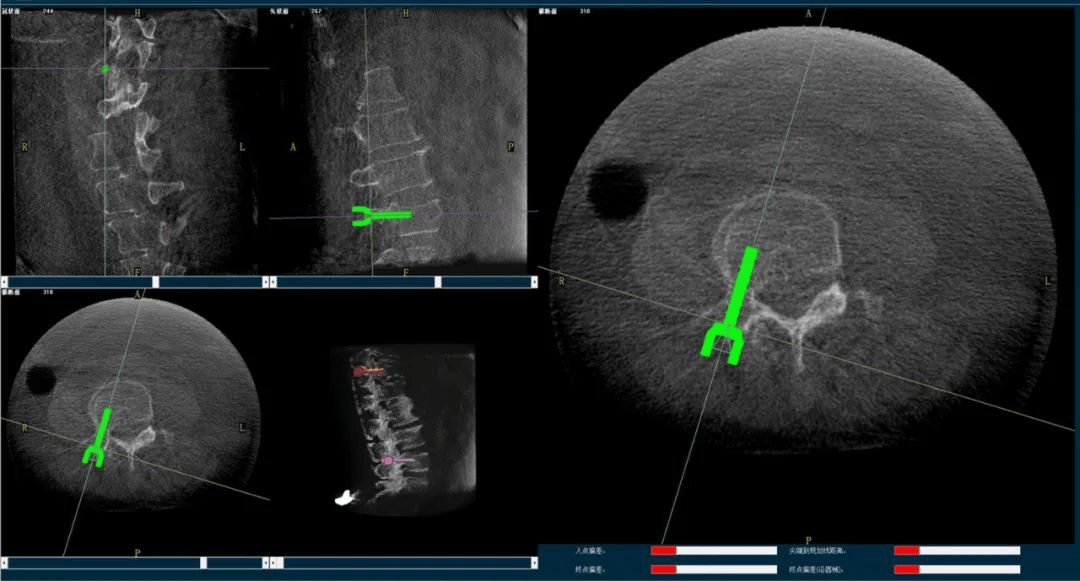

術(shù)中,手術(shù)團(tuán)隊(duì)先對(duì)患者進(jìn)行三維影像掃描,將圖像同步傳輸至機(jī)器人成像系統(tǒng)后,利用骨科手術(shù)機(jī)器人導(dǎo)航系統(tǒng)做好手術(shù)規(guī)劃,隨后利用其機(jī)械臂,將手術(shù)工具精確定位到“目的地”,鋪好“通道”,這就很好的解決了醫(yī)生“盲穿”的問(wèn)題。

主任為患者注射骨水泥,再次影像掃描后,發(fā)現(xiàn)骨水泥進(jìn)入位置非常好,彌散效果更佳,手術(shù)順利完成,患者的恢復(fù)也自然更好。